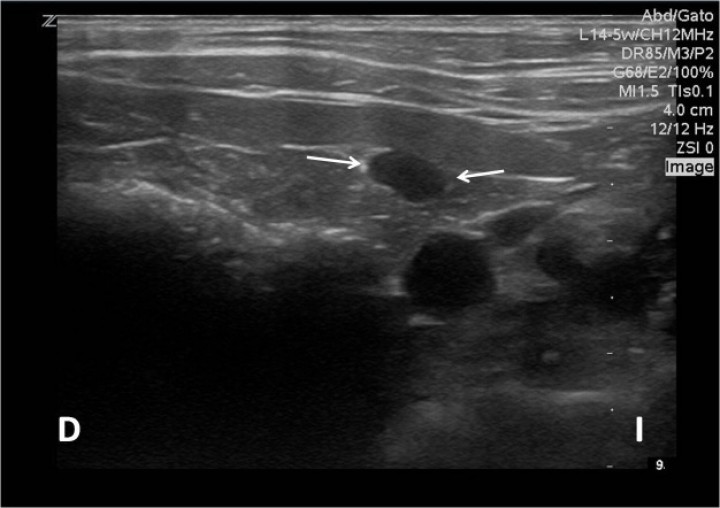

La ecografía abdominal (Fig. 2), realizada con sonda lineal de 5 - 14MHz (Z.one ultra, ZONARE, Mountain View, CA, EE. UU.), reveló un vaso anómalo con origen en la vena esplénica a nivel del hilio esplénico que se dirigía hacia caudal y a nivel del polo craneal de la vejiga presentaba un recorrido tortuoso, tras el cual parecía bifurcarse y rodear a la misma para continuar hacia caudal. El hígado presentaba un parénquima discretamente hiperecogénico de forma difusa con múltiples nódulos hipoecogénicos redondeados de bordes irregulares. La vena porta presentaba un flujo hepatopetal y su velocidad se encontraba dentro de los límites normales (23 cm/s), descartándose la presencia de hipertensión portal. El ratio porta/aorta fue de 0,89. Se observó así mismo urolitiasis vesical.

<div class=\"Basic-Text-Frame\">

<p>Imagen ecográfica en un corte transversal en abordaje ventral donde se observa una estructura tubular anecógena adyacente al bazo (flechas). D: derecha, I: izquierda.</p>

</div>

Figura 2

Imagen ecográfica en un corte transversal en abordaje ventral donde se observa una estructura tubular anecógena adyacente al bazo (flechas). D: derecha, I: izquierda.